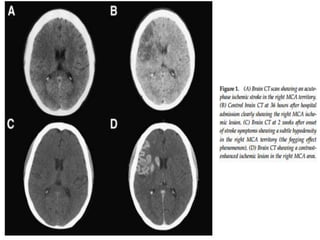

1-8 weeks

 Contrast enhancement persists.

 Mass effect resolves.

 The swelling starts to subside and small amounts of

cortical petechial hemorrhages results in elevation of

the attenuation of the cortex. This is known as the CT

fogging phenomenon .

 Imaging a stroke at this time can be misleading as the

affected cortex will appear near normal.

2’nd and 9’th days post stroke

images